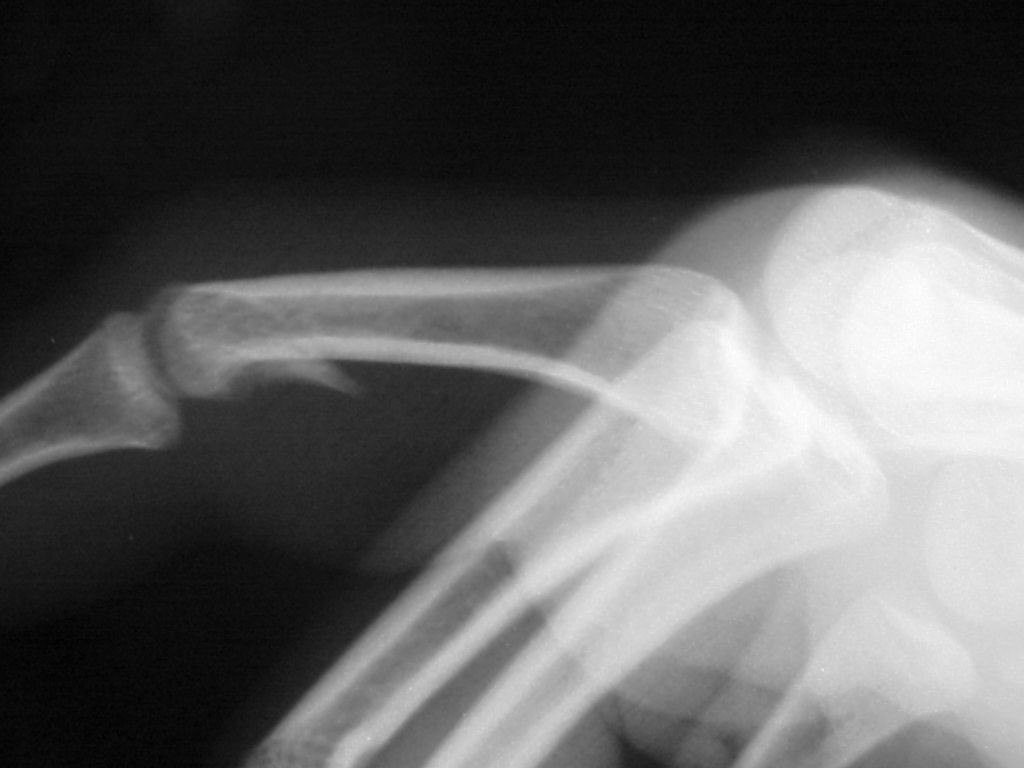

Clinical Example: Unicondylar proximal phalanx head fracture with micro screws

Unicondylar fractures of the phalangeal head are common, frequently unstable and unacceptably displaced. Although some may be treated successfully with percutaneous reduction and fixation, many require open reduction. In these cases, the screws were put right through the collateral ligament and sunk into the cortex. I think the simplest way to do this is to reduce and stabilize with two K wires, then remove the wires and replace with screws, one at a time, so reduction is maintained throughout. 1mm=39/1000" Kwire, so doing the math, here is how you choose the right sized Kwire to use as both drill and provisional fixation:

Case 2.

And another patient.